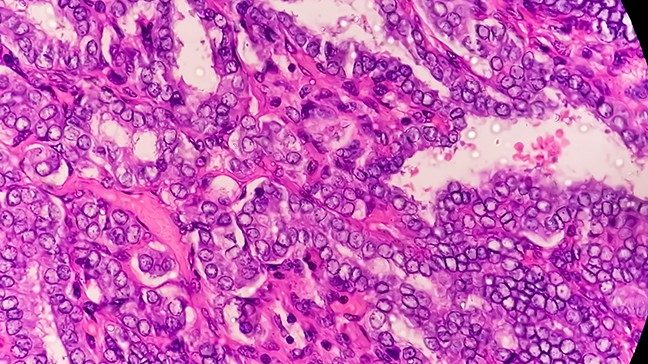

Squamous cell carcinomas: 8 things to know about the ‘cancer of the surfaces’

Much like adenocarcinomas, squamous cell carcinomas can develop in many locations, including the skin, lungs and cervix.

Unlike...